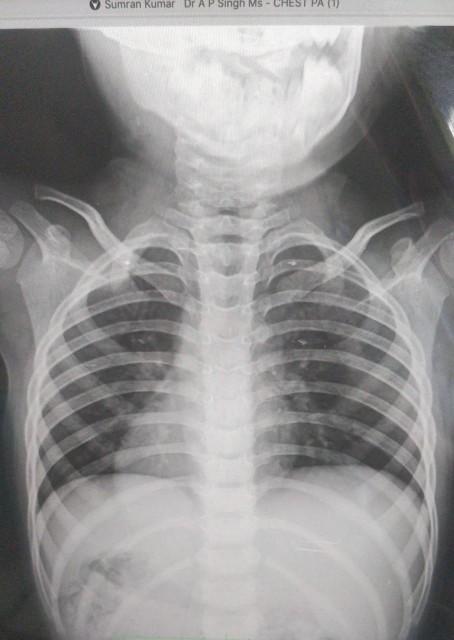

Radiographers/technitians are taught from day one in school to place anatomical markers within the primary beam of radiographs. We do so as a method of "best practice" to properly distinguish the patient's right from left on the radiographic image per legal requirements. Conditions like Dextrocardia (when the heart is positioned on the right instead of the left) and situs inversus (when all of the internal organs are on the opposite side compared to normal anatomy) as shown in Pic 02 exist which can easily be misinterpreted and would normally cause a technologist to inappropriately orient the image to appear similar to normal anatomy. But when radiographs misrepresent right from left, this presents a huge risk for medical errors.

Pic 02: Flipped Xray : By mistake above image can be taken as Dextrocardia situation meaning heart on different side of the body: